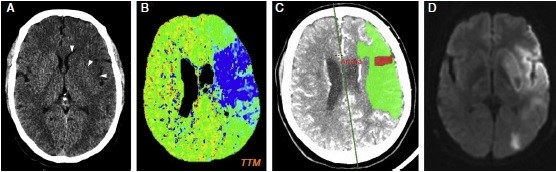

Se pueden mencionar al respecto los estudios que han encontrado en pacientes dependientes al alcohol una disminución del volumen de sustancia gris en el área de la corteza frontal, el hipocampo y el tálamo. El volumen de las sustancias blanca y gris también se puede ver disminuido en el área periventricular, la protuberancia y el cerebelo. Estos déficits de volumen también se han localizado en la corteza prefrontal dorsolateral derecha, ínsula anterior derecha, en el núcleo accumbens y en la amígdala izquierda(16) (ver Imagen 1).

Asimismo, como se indicó previamente, a través de la TC también se puede observar el deterioro de la microestructura cerebral por adicción al alcohol. El abuso de esta sustancia altera cinco fibras del cerebro, como el cuerpo calloso, el fondo de saco, la cápsula externa, el cíngulo circunvolución y el fascículo longitudinal superior, las que están involucradas en funciones como el procesamiento visoespacial y del lenguaje, la comunicación interhemisférica, la memoria, el procesamiento emocional, la toma de decisiones y la integración sensorial(16) (ver Imagen 2).

Asimismo, una investigación encontró patrones comunes de lesiones cerebrales a través de la neuroimagen mediante una recopilación extensa de estudios radiológicos vinculados con casos de adolescentes con problemas de adicción a sustancias psicoactivas ilegales, desde 2006 hasta 2016. El estudio constató dos patrones coincidentes. El primero fue la lesión cerebral difusa simétrica de la sustancia blanca subcortical con afectación cerebelosa preferencial, o leucoencefalopatía. El segundo lo constituyen múltiples focos de infartos isquémicos en una distribución territorial no arterial patrón isquémico.(21)

En esta investigación que se viene señalando, se puede mencionar el caso de un joven de 16 años, con alteración aguda del estado mental por inhalación de vapor de heroína. Se le efectuó una RM que evidenció hiperintensidades en T2 de la sustancia blanca simétrica difusa infratentorial y supratentorial. El diagnóstico clínico en este caso fue rabdomiólisis, que afecta predominantemente la musculatura posterior del cuello(21) (ver Imágenes 11 y 12).

Otro caso que merece ser comentado es el de un adolescente de 15 años que presentó encefalopatía y signos extrapiramidales por ingestión de metadona. La RM evidenció focos de infartos agudos en el caudado y putamen, así como infartos corticales de la línea divisoria de aguas parietales(21) (ver Imagen 13).